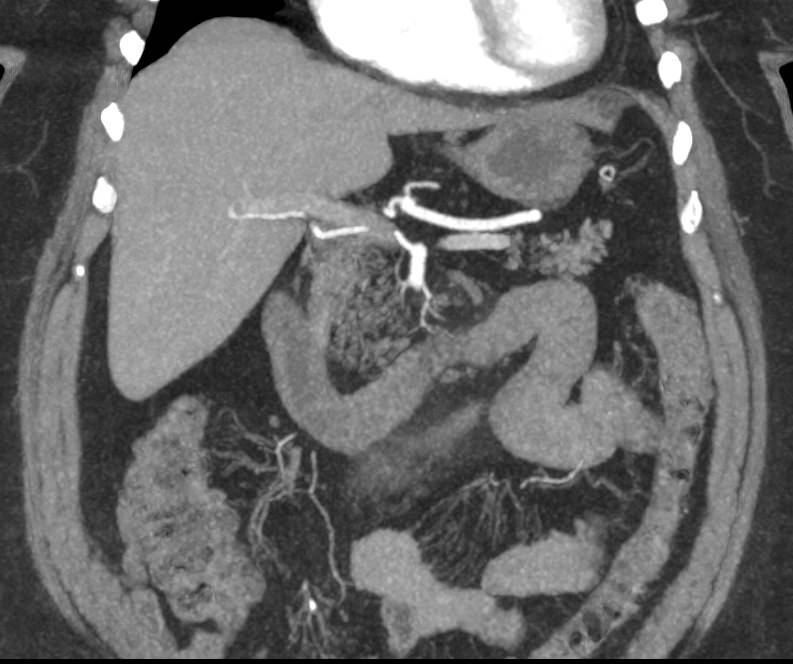

В брюшной полости и забрюшинном пространстве расположены группы лимфатических узлов, которые окружают внутренние органы (желудочные, печеночные, брыжеечные, чревные, подвздошные и др) и располагаются вдоль крупных кровеносных сосудов. Лимфоузлы относятся к периферическим органам иммунной системы человека и выполняют защитную функцию, являясь барьером для проникновения инфекций и задерживают распространение раковых клеток.

Патологические изменения регионарных лимфоузлов часто свидетельствуют о поражении того органа, от которого происходит лимфоотток. Это имеет важное значение для оценки распространенности онкологического процесса, выявления отдаленного метастатического поражения лимфатической системы, а также используется для определения тактики лечения. Кроме того, патология лимфатических узлов может говорить о развитии гемобластозов и лимфопролиферативных заболеваний крови.

Компьютерная томография позволяет детально визуализировать структуру лимфатических узлов, выявить ее неоднородность, гиперплазию, определить деформацию контуров, появление инфильтрации окружающих тканей с образованием пакетов и конгломератов лимфоузлов.